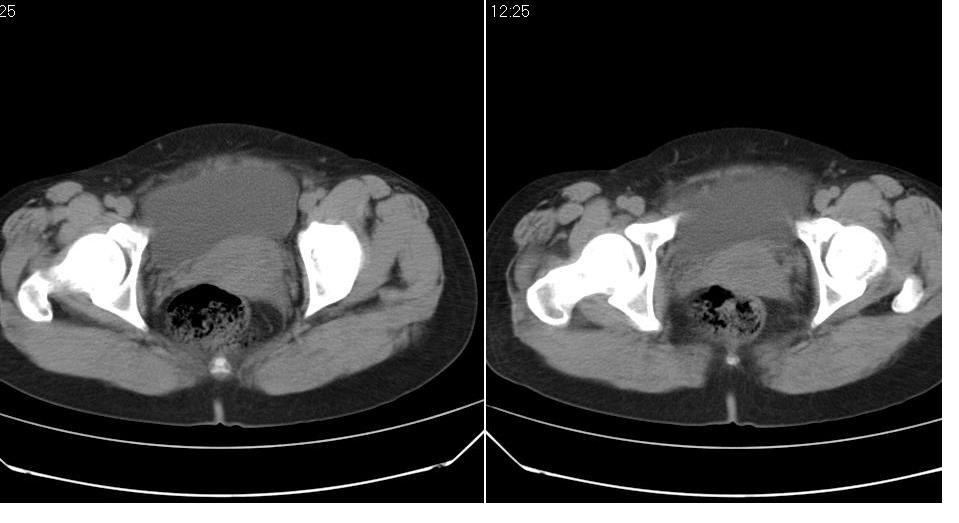

女 35岁,下腹部坠感疼,其它病史不详。图象顺序有点乱。

考虑右侧卵巢畸胎瘤。

定位于盆腔附件,有囊性密度,有脂肪密度、还有骨密度;应该是比较典型的卵巢畸胎瘤。